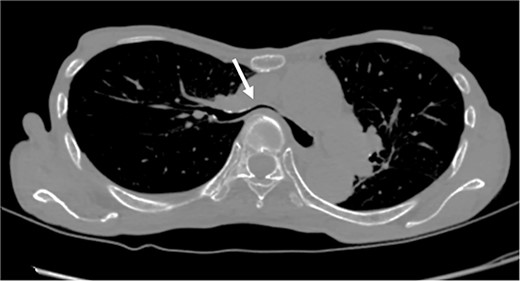

The patient was a 74-year-old woman with a history of childhood PE. Fourteen years ago, a total glossolaryngectomy was performed at another hospital for oropharyngeal cancer, and a permanent tracheal stoma was created. Approximately 2 years later, the patient gradually experienced difficulty in breathing. Chest computed tomography (CT) revealed severe PE and right main bronchial stenosis. Subsequently, the patient was referred to our department. A preoperative spirometry test showed a vital capacity of 1.14 L (45% of the predicted value). As part of the imaging test, a chest CT indicated a leftward deviation of the trachea. Symmetrical depression with a Haller Index (HI) of 8.9 and stenosis of the right main bronchus were observed at the same site (Fig. 1). The chest CT taken over 8 years indicated that the leftward deviation of the trachea had progressed and the thoracic depression had worsened (Fig. 2). Intraluminal observation using a bronchoscopy revealed severe stenosis of the right main bronchus, making peripheral observation challenging (Fig. 4A).

Chest CT findings of severe PE with stenosis of the right main bronchus. The right main bronchus was severely narrowed with a HI (HI) of 8.9 (arrow).